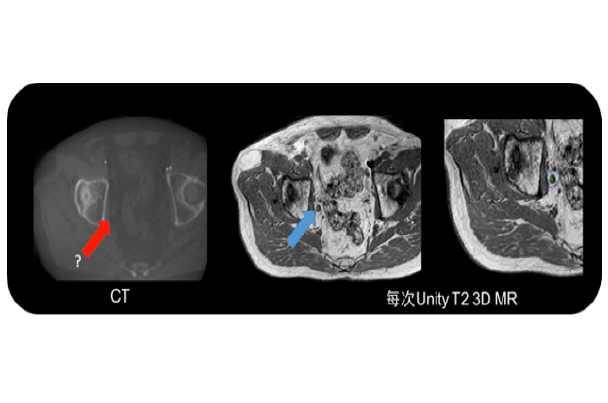

随着生活水平的提高,前列腺癌大发病逐渐上升,剂量学研究和初步的临床实践已经显示调强是当今放疗前列腺癌的最好照射技术,有广泛的应用前景,磁共振引导技术可以更好的对前列腺组织进行分辨,可以进行功能保留行治疗及肿瘤消融治疗,同时磁共振功能成像技术也为治疗疗效提供生物学依据。